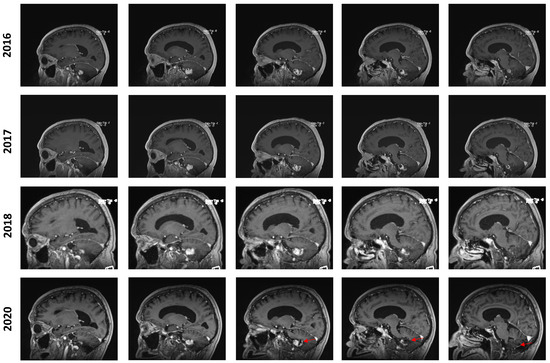

In July 2016, an MRI showed a mild increase in the lesion’s size from 24 × 17 × 17 mm to 26 × 20 × 17 mm (AP, T, CC, respectively). In the yearly imaging follow-ups, the lesion was found to be slowly shrinking, reaching a size of 18 × 13 × 14 mm in September 2020. However, at this time, the lesion still displayed a prominent cystic component that appeared to be slightly progressive. In retrospect, it appears that the solid component of the lesion remained stable while the cystic component was discreetly progressing, especially from 2018 to 2020 (Figure 2). No new lesions were found during the clinical course of the patient.

Figure 2. Longitudinal follow-up. Representative capture of sagittal T1-weighted MRI control imaging. The date of imaging is represented. Images are organized left to right and represent a left–right progression in the sagittal plane. The red marker highlights the appearance of an enlarging cystic component in the posterior aspect of the lesion in 2020.